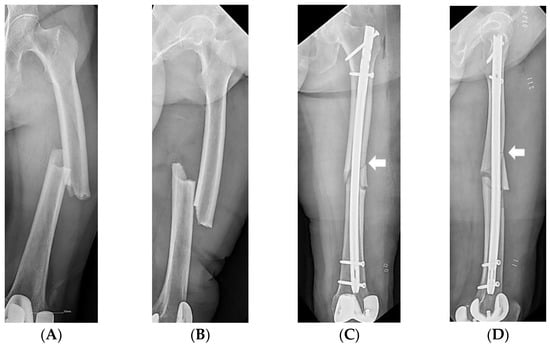

| Nail entry point Greater trochanter, n | 17 (85.0%) | 62 (82.7%) | 1.000 |

| Piriformis, n | 3 (15.0%) | 13 (17.3%) | 1.000 |

| Nail diameter, mm | 11.9 ± 1.2 (9–13) | 11.5 ± 1.4 (9–14) | 0.185 |

| Nail length, mm | 334.0 ± 27.6 (280–380) | 336.0 ± 23.5 (280–380) | 0.745 |